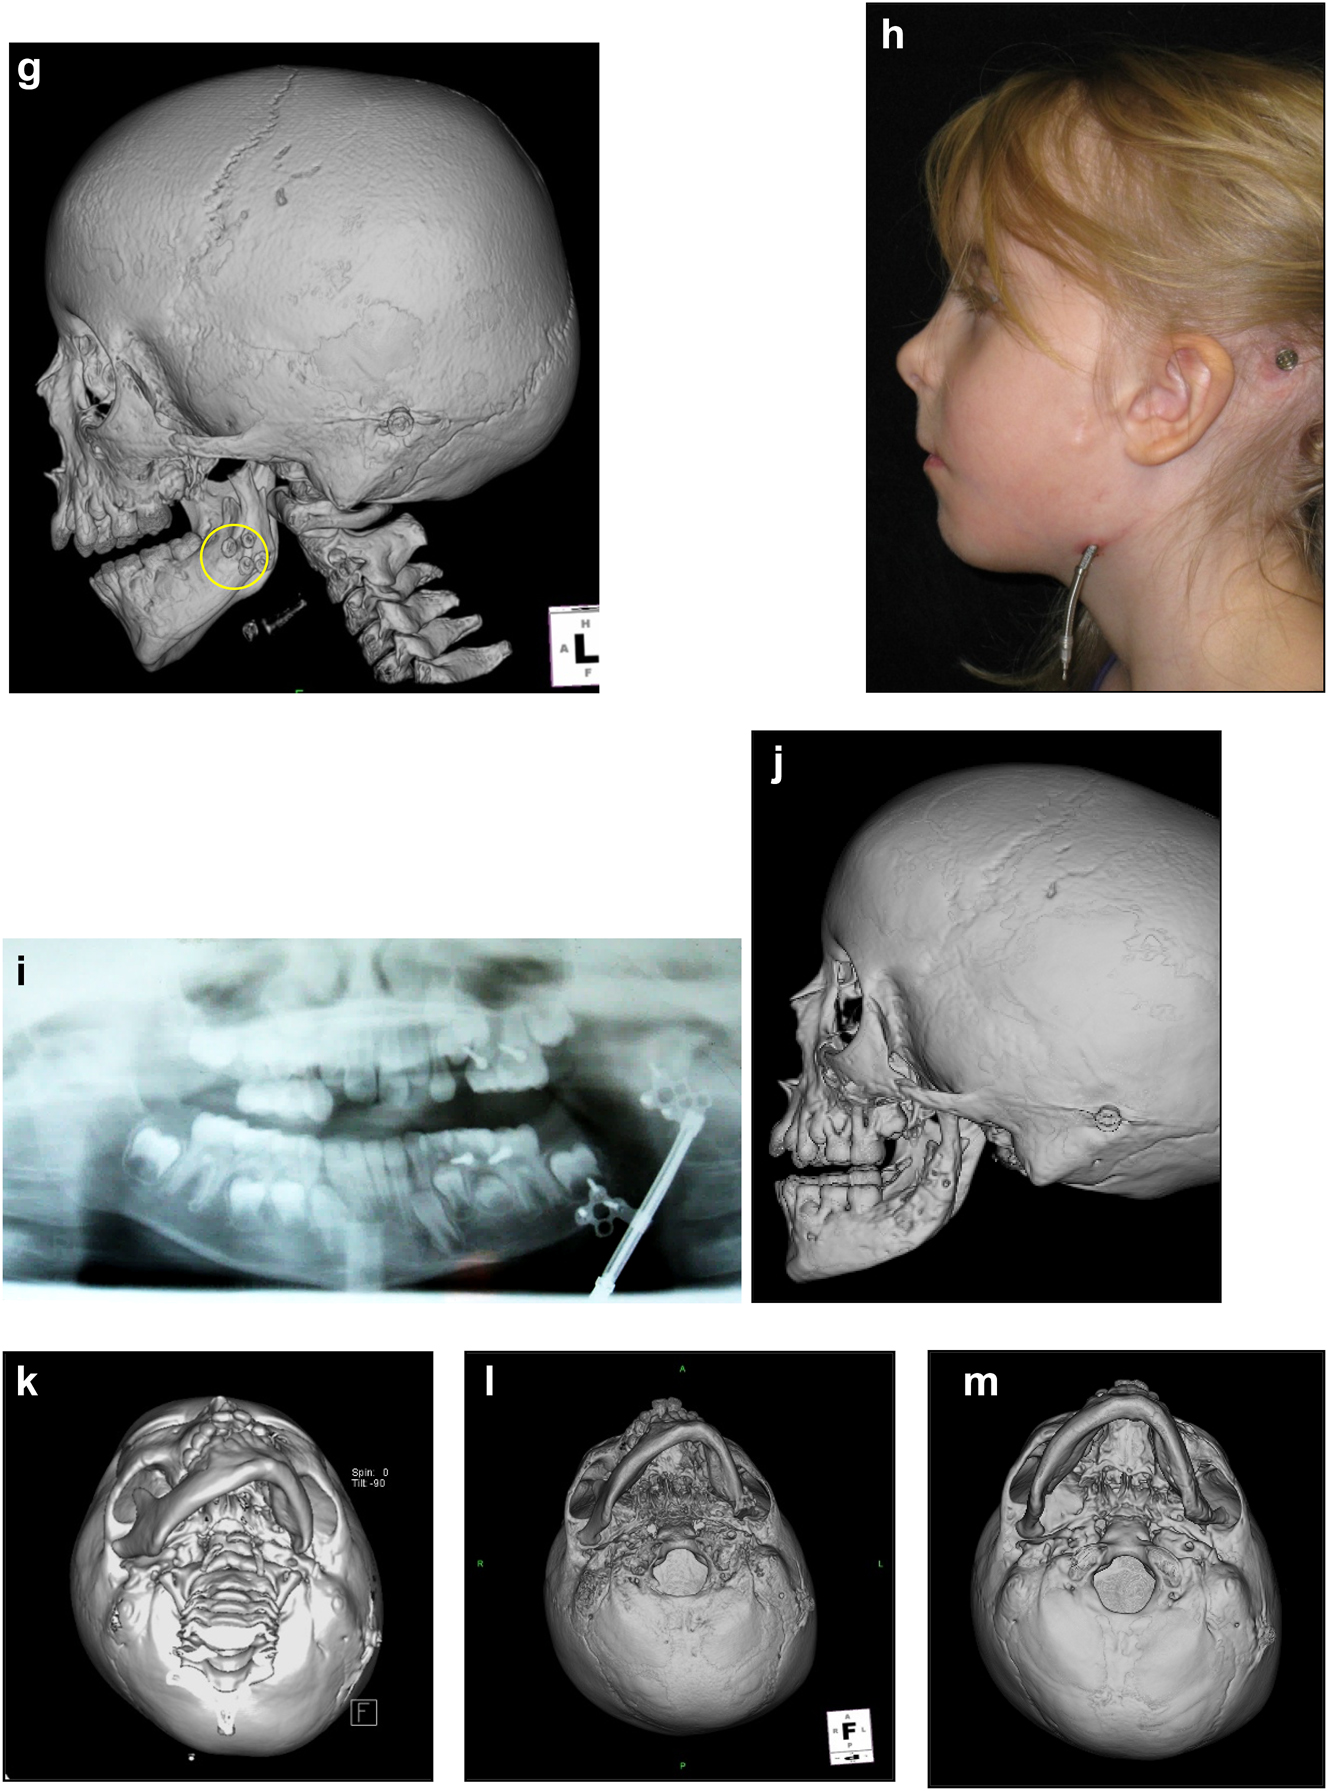

The further case below (Figures 20 and 21) is a PK III or IIb HFM. Please note the bone anchored hearing aid abutment in situ. She initially received a costo-chondral graft [34] to the left mandibular ramus.

Figure 20:

Construction of a HFM child with a costo-chondral graft followed by ramus lengthening by DO (a–f).

Construction of a HFM child with a costo-chondral graft followed by ramus lengthening by DO (g) Yellow ringed area is where the rib graft overlaps the original mandibular bone – the correct site for the DO osteotomy while avoiding any tooth germs. (h) Percutanous distractor port in situ. (i), (j), (k–m) Submental view of mandibular shape and position pre rib graft (k), post rib graft (l), post distraction (m).

Later she required vertical lenghtening of the left mandibular ramus by distraction and, as described on Page 11, it is important to perform the osteotomy for that distraction within the original mandibular bone and not in the consolidated rib graft, in the area ringed in yellow on the post-rib graft CT scan below (Figure 21).